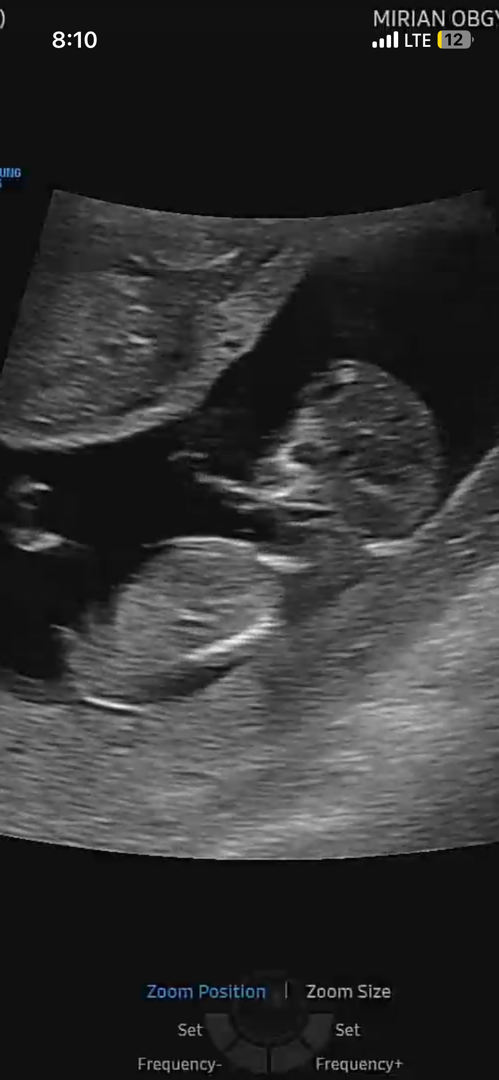

이사진으로 알수있을까용 도대체 각도법이 뭐죠 ..? 촘파는 11주때 사진이에요 ..ㅜㅜ